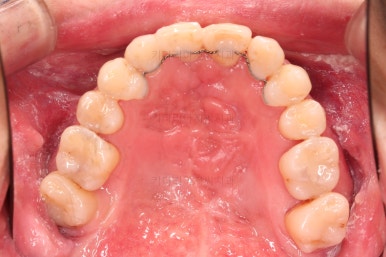

1. 초진 시 입안의 모습

부산구순구개열교정 키다리아저씨치과에 처음 내원하셨을 당시의 입안의 모습입니다.

구순구개열 환자분의 일반적인 입 안의 특징은 다음과 같습니다.

골 결손부위의 치아 결손이 빈번하다.

구개열 봉합술을 어린 나아이에 받기 때문에, 해당 부위의 상흔이 남는다.

상흔의 영향으로(피부 상처도 일반 피부 보다는 상처가 아문 부위가 더 단단하죠.) 입천장의 잇몸이 굉장히 단단하다.

그래서 가로폭의 성장이 잘 되지 못하여 악궁(치아가 배열된 U자 형태)이 협착된 경우가 많다.

공간 부족으로 치열이 매우 삐뚠 경우가 많다.

공간 부족과 악궁 형태 등으로 인해 부정교합이 함께 나타난다.

골 결손부위 근처의 치아는 뼈가 약한 경우가 많아 튼튼하지 못하고 만지면 흔들리는 경우가 많다.

이번 환자분도 이와 같은 일반적인 특징이 그대로 나타나 있었습니다.

양측성 구순구개열이었으므로 작은 앞니(대문니와 송곳니 사이)가 양쪽 다 결손이었고, 또 다른 이유로 아래 앞니도 1개 없는 상태였습니다.